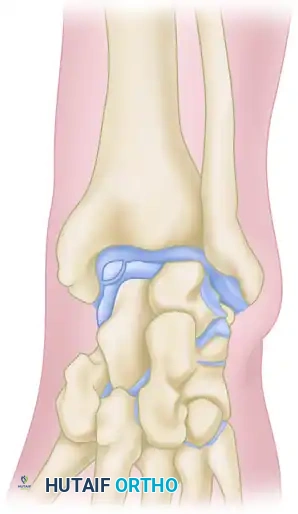

In 1957, O’Donoghue formally directed the orthopedic community's attention to a previously underreported cause of chronic ankle disability: the formation of osteochondral ridges, or exostoses. These bony proliferations typically develop just proximal to the anterior lip of the distal articular surface of the tibia and on the corresponding opposing area of the dorsal surface of the talar neck.

Predominantly observed in athletic populations—particularly footballers, dancers, and runners—these ridges are primarily driven by repetitive biomechanical stress. According to O’Donoghue, the primary etiology is direct mechanical injury sustained during forceful, extreme dorsiflexion of the foot, wherein the neck of the talus is violently thrust against the anterior tibial plafond. Repeated minor microtraumas precipitate a hypertrophic bone response, causing these ridges to enlarge over time. As the exostoses grow, the threshold for collision between the talus and tibia decreases, creating a self-perpetuating cycle of impingement, cartilage abrasion, and further osteophyte formation. These ridges may manifest in isolation on the tibia or the talus, but frequently develop concomitantly on both articular surfaces.

Anterior impingement syndrome is classically an overuse injury of the dorsiflexors, compounded by repetitive microtrauma. The mechanical abutment of the anterior tibial margin against the talar neck leads to the formation of "kissing lesions" or osteophytes.

Scranton and McDermott developed a widely utilized radiographic classification system for anterior ankle spurs, which correlates directly with the degree of joint involvement, treatment complexity, and prognostic recovery:

Grade I (Synovial Impingement): Radiographs demonstrate an inflammatory reaction with minor tibial spurs measuring up to 3 mm.

Grade II (Osteochondral Reaction Exostosis): Radiographs show tibial spurs larger than 3 mm. No corresponding talar spur is present.

Grade III (Severe Exostosis): A secondary spur is noted on the dorsum of the talus, often accompanied by fragmentation of the osteophytes (kissing lesions).

Grade IV (Pantalocrural Osteoarthrotic Destruction): Radiographs suggest diffuse degenerative osteoarthritic changes extending medially, laterally, or posteriorly, indicating global joint deterioration rather than isolated impingement.